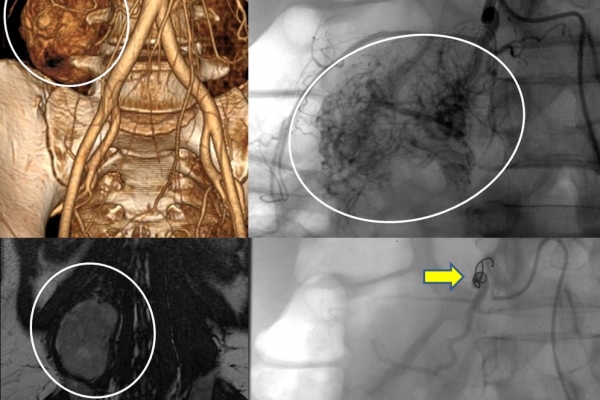

♦ Όγκους

Είτε προεγχειρητικά για την ελάττωση της αιμάτωσης του όγκου, είτε θεραπευτικά σε ορισμένες περιπτώσεις που δεν απαιτείται χειρουργείο ή υπάρχει αντενδειξη για χειρουργική αφαίρεση του όγκου.

Συνοπτικά υπό την καθοδήγηση του αγγειογράφου, αναγνωρίζεταιτο παθολογικό αγγείο-αγγεία και με ειδικούς καθετήρες και μικροκαθετήρες, διοχετεύονται εμβολικά υλικάόπως μικροσφαιρίδια ή coils, ώστε να αποφραχθεί ή να μειωθεί η παθολογική αγγείωση.